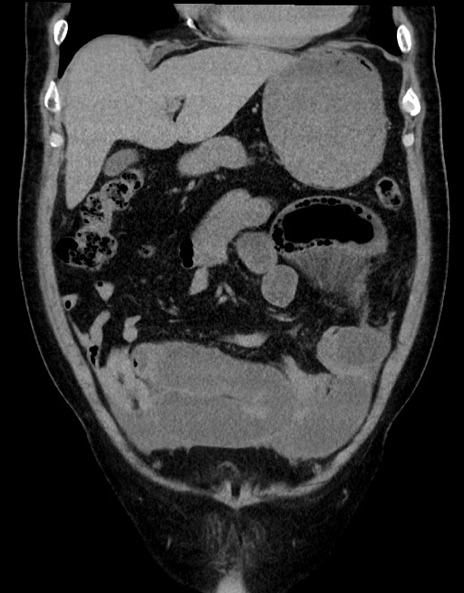

横断像

症例15(冠状断像)

【症例】70歳代男性

【主訴】腹痛

【現病歴】今朝から腹痛あり。全体的に痛い。特に左上の方。排ガスが今日はない。冷や汗が出る。

【既往歴】直腸癌術後

【身体所見】左側腹部〜上腹部に圧痛あり。腹膜刺激症状明らかなではない。軽度反跳痛。左下腹部に術後瘢痕あり。

【データ】WBC 7700、CRP 0.02